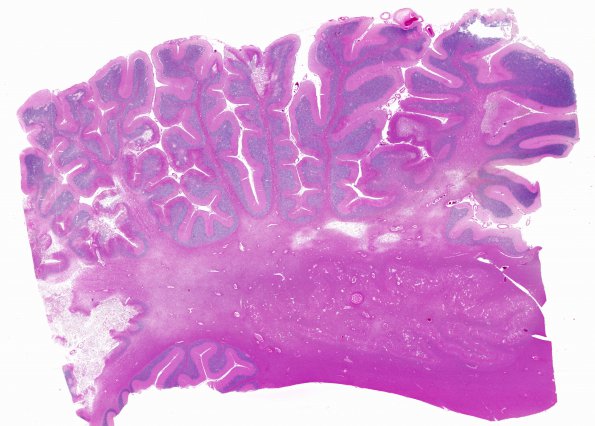

7B1 Arteriolosclerosis (Case 7) N9 H&E WM

This image shows patchy areas of infarction. (H&E)